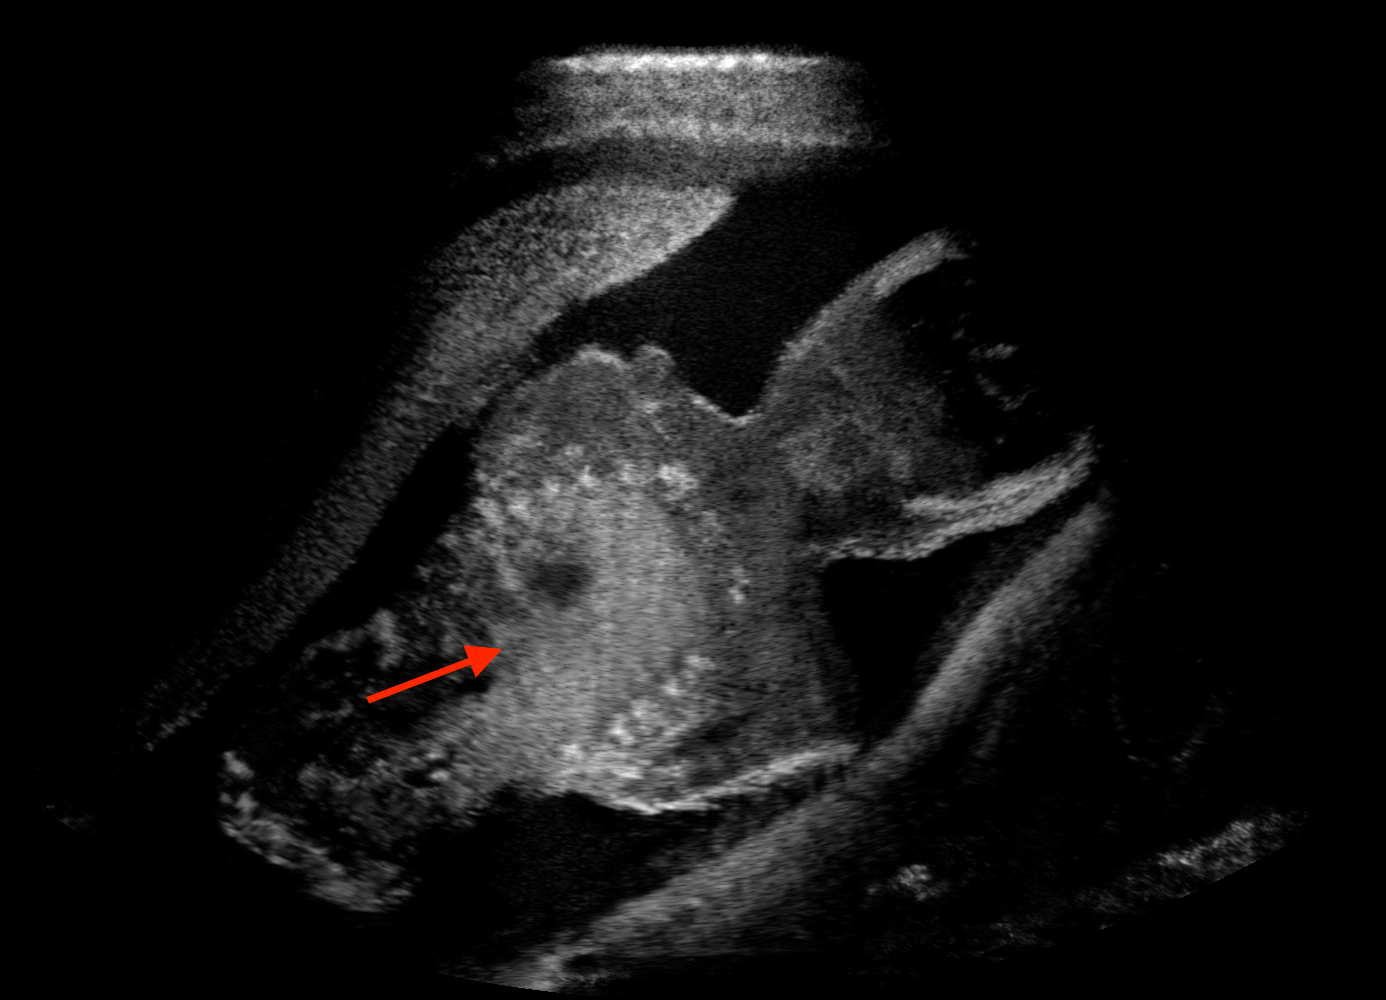

Qualitative evaluation.

Fig. 2 depicts the qualitative results for all the models mentioned above, with arrows pointing at structures relevant to discussion points below. The visual results of the ablated variants of SA2H show substantial quality degradation compared to the full SA2H model, demonstrating the importance of each proposed architectural contribution. Given only segmentation map in the network input, SA2H-att fails to generate acoustic shadows, e.g. those cast by the ribs. Detailed structures such as the cervical vertebrae are blurred out in the SA2H-concat results, which also contain hallucinated structures mainly due to insufficient preservation of input information along the encoding-decoding path. With SA2H-conv, checkerboard artefacts are observed due to the lack of proposed additional stride-1 convolutional layers. SA2H-noise without any explicit noise input is seen to be sub-optimal at generating textural details. The baseline method NSA2H fails to preserve anatomical structures and acoustic shadows in all cases, while the simulated textures also show significant artefacts such as checkerboard patterns. Realism of different simulation aspects may become relevant given different clinical applications and scenarios. For instance, improved structural preservation, e.g. with the hyperechoic bony structures such as the skull and the ribs, of the final model over its ablated variants and NSA2H may prove relevant in fetal head measurements, while the textural improvements facilitating screening fetal organ maturity, e.g. lungs. Compared to the silver-standard model LSA2H with a low-quality rendered image as additional input, SA2H is seen to be on par in structural preservation. Note that shadowing on homogenous regions (e.g. the rib shadowing on the homogenous lung region on the 4th column of Fig. 2) with our proposed method SA2H is represented more faithfully compared to LSA2H, whereas shadows on structurally complex regions (e.g. the skull shadowing around the heart and surrounding tissues on the 3rd column of Fig. 2) are suboptimal with our SA2H. Therefore, one may have to evaluate our method given particular simulation tasks, e.g. its clinical validity for fetal heart exams. However, even with low quality rendered images, LSA2H leads to artificial enhancements of intensities, lack of acoustic shadows, and low-quality textures especially near the probe, for which SA2H yields satisfactory results as illustrated in Fig. 2.

(a) Target

(b) SA2H

(c) SA2H-att

(d) SA2H-concat

(e) SA2H-conv

(f) SA2H-noise

(g) NSA2H

(h) LSA2H